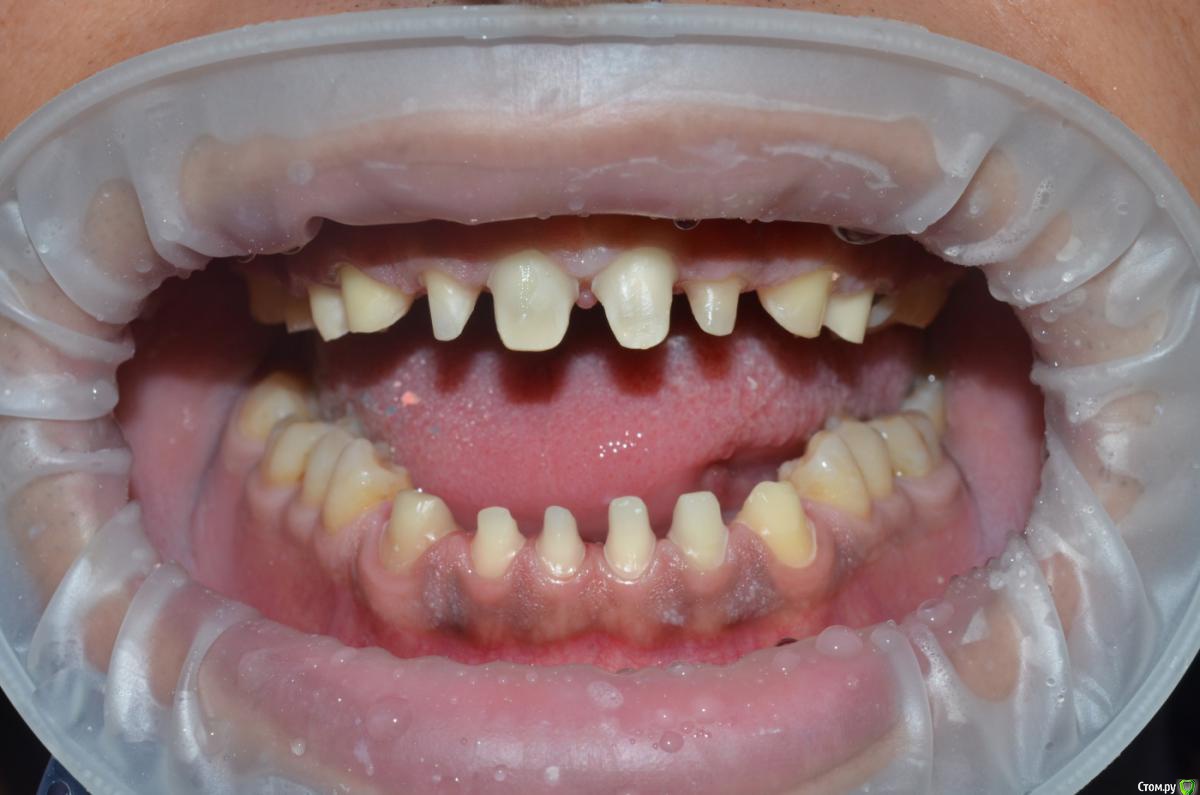

NazranDantist Опубликовано 4 сентября, 2015 Поделиться Опубликовано 4 сентября, 2015 К сожалению фото до где-то потерялись, были очень длинные клыки, смыкались по типу ножниц. Пришлось поднимать прикус на 0.6-0.8 мм. Обточка, времянки, слепки - 3 часа, фиксация 2 часа, без примерок на готово. Пациент попросил "ахпер, сделай две белый полосы, как на моем камаро" . Все циркон с вестибулярной облицовкой, фиксация Фуджи+. Фоткал пока цемент еще застывал.Учимся работать по китайскому протоколу, тотал за неделю и за 3000$ 1 1 Ссылка на комментарий

NazranDantist Опубликовано 4 сентября, 2015 Автор Поделиться Опубликовано 4 сентября, 2015 На 21 скол по режущему медиально?Да, при проверки движений суперконтакт выявился. резинкой после заполировали. Ссылка на комментарий

Freelancer1981 Опубликовано 4 сентября, 2015 Поделиться Опубликовано 4 сентября, 2015 Почему центральные резцы желтее остальных(нижние тоже)?Одним нельзя было сделать?Форма клыков меня смущает..И почему то мне кажется что при латеротрузии контакт у вас не только на клыках есть но и на двойках.. Ссылка на комментарий

NazranDantist Опубликовано 4 сентября, 2015 Автор Поделиться Опубликовано 4 сентября, 2015 Пациенту понравилось. Эстетика не супер, я ж говорю, делалось за три дня и за ограниченный бюджет, в 18:00 - достали из печки после глазури, в 21:00 пациент уехал (час на транспортировку работы), еще не дорос до того уровня, чтоб выбирать пациентов . С десной все ок, фото препа - перед фиксацией (можете обратить внимание на десну), фото после - только, только цемент начал стыть. Перед этой работой читал про то, как наши граждане ездят в китай лечить зубы, и все думал, как это за 3-5 дней там делают тоталы. Теперь я это знаю . 1 Ссылка на комментарий

RuStom Опубликовано 4 сентября, 2015 Поделиться Опубликовано 4 сентября, 2015 Зубы все депульпированы?как удается препарировать столько зубов за 3 часа с времянками и слепками?лично у меня все гораздо медленнее идет... 1 Ссылка на комментарий